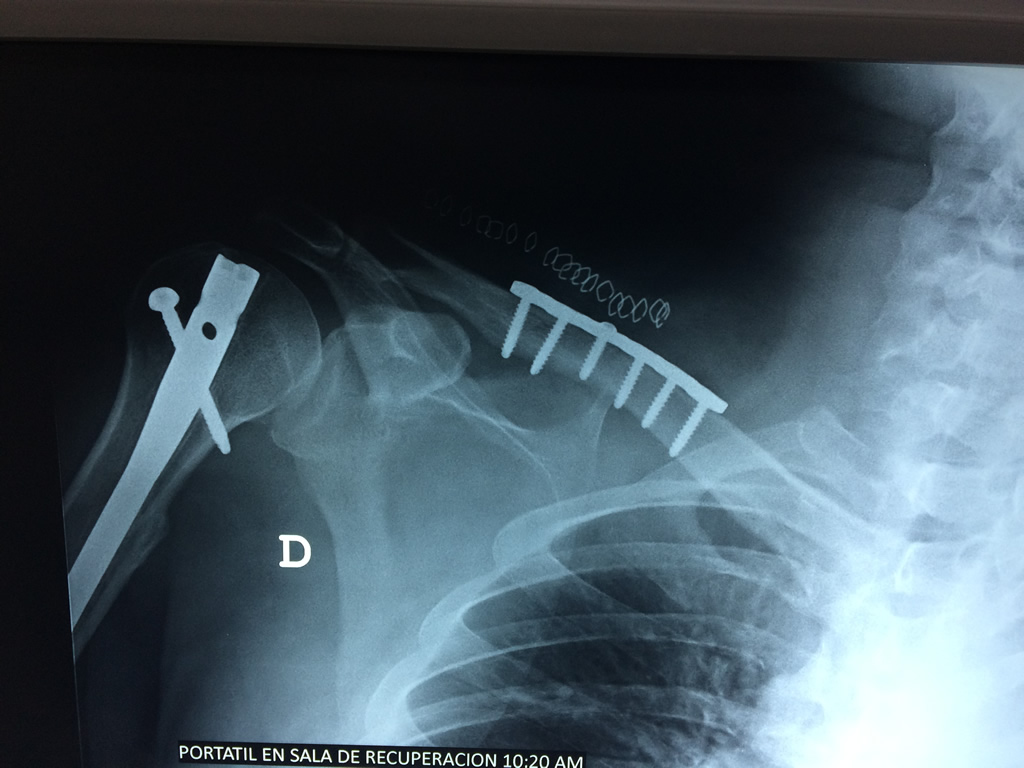

Cirugías

La clavícula es un hueso largo, con forma de "S" itálica, situado en la parte anterosuperior del tórax. Junto con la escápula forman la cintura escapular. Se puede palpar por toda su longitud y se extiende del esternón al acromion de la escápula, siguiendo una dirección oblicua lateral y posterior.